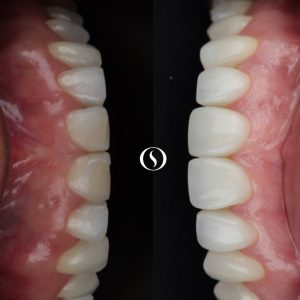

Trabalhamos com procedimentos estéticos, tais como: Clareamento Dental, Lentes de Contato Dental e Facetas em cerâmica e resina.

A implantodontia é um procedimento odontológico que envolve a colocação de implantes dentários de titânio no osso maxilar ou mandibular para substituir dentes perdidos. Os implantes proporcionam uma base sólida para a fixação de coroas, pontes ou próteses, restaurando a função mastigatória, estética e saúde bucal do paciente.